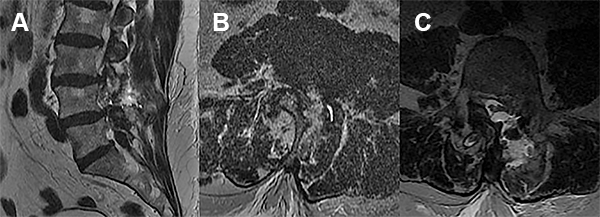

Por imágenes de resonancia magnética se evidenciaba estenosis de canal lumbar, discopatía degenerativa multinivel y espondilolistesis L4/L5.

Se decidió internación para valoración clínica y por imágenes. Por resonancia se evidenció colección de LCR en el sitio de la reparación dural (fig. 1).

Figura 1

En el presente trabajo, los autores reportan un evento hemorrágico cerebral como complicación de una fistula de líquido cefalorraquídeo (LCR) asociada a una cirugía espinal lumbar mini invasiva. Dicho evento se desencadenó 72 hs luego de la reparación de la fístula de LCR, presentándose como una hemorragia subaracnoidea de la convexidad cerebral. Esta complicación ha sido descrita por numerosos grupos,1-5 siendo la localización mas frecuente el cerebelo. Si bien las imágenes de tomografía y resonancia magnética nuclear evidencian la presencia de hemorragia subaracnoidea en el surco central derecho, llama la atención la asimetría de surcos con hipodensidad en el área premotora derecha, similar a los hallazgos asociados con una trombosis venosa. Más aún, considerando que el paciente tiene antecedentes de trombosis venosa profunda e ingresa a las 72 horas por trastornos del sensorio (difícilmente explicables sólo por una hemorragia subaracnoidea de la convexidad), no podemos descartar con las imágenes brindadas la presencia de trombosis venosa, complicación también descripta como consecuencia de una perdida de LCR.6-9 Si bien ambas complicaciones son de muy baja ocurrencia, es importante reconocer su existencia a la hora de evaluar un postoperatorio de cirugía espinal complicado con fistula de LCR en pacientes añosos.